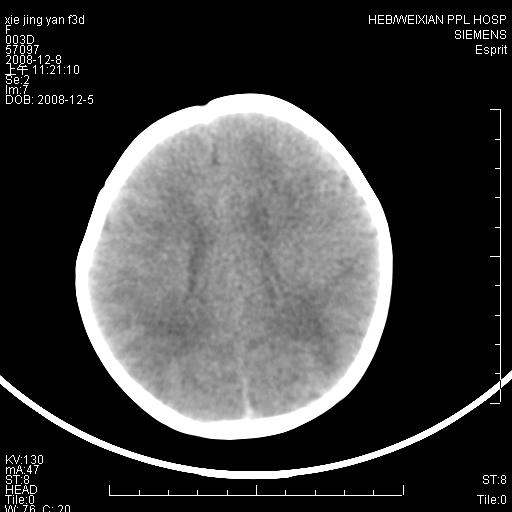

标题: PED1679:最小的“脑梗死”患者,能下其他诊断吗?

女,三天。呕吐,右侧上肢抽搐5小时。新生儿缺氧缺血性脑病有这样在基底节区出现缺血性表现的吗,并且有一侧肢体症状。

病灶局限,余脑质密度均匀,灰白质分界可.考虑脑梗死

一侧肢体有症状,而且发生在灰质,边界较清晰。还是先考虑脑梗死!~!建议mri检查